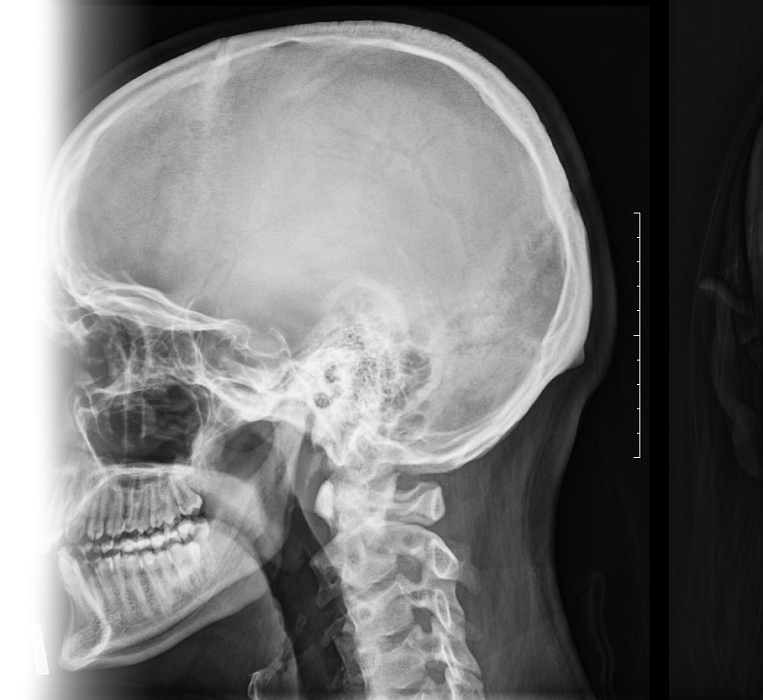

Рентгенография черепа – важный метод рентгенологического исследования состояния различных костных зон черепа.

1. Рентгенография черепа стандартная

Стандартное рентгенологическое исследование костей черепа в двух проекциях.